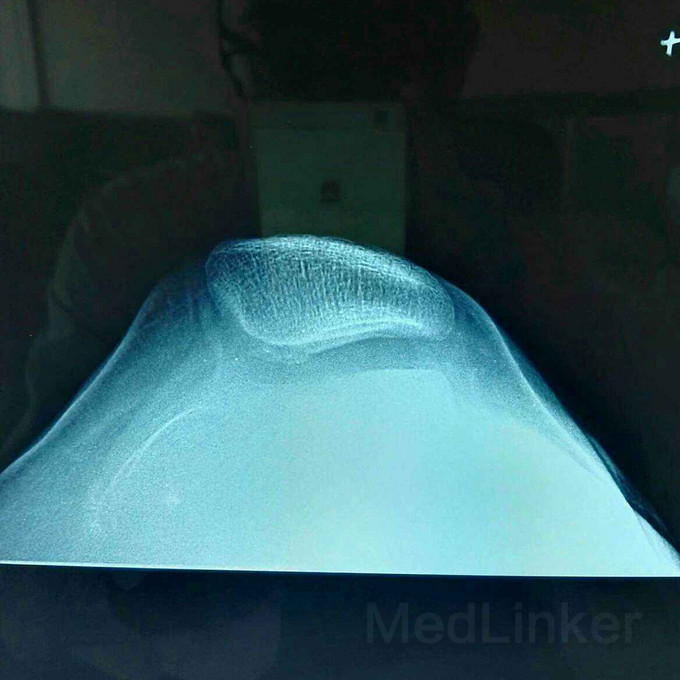

髌骨脱位的治疗?

髌骨脱位

患者女,19岁,双膝关节习惯性髌骨脱位10余年,多家医院建议手术治疗,2个月前摔伤致左髌骨脱位,于某院行手术治疗,经家人商讨后决定再行右膝手术治疗来我院。请老师们指点是否需要调整髌骨远端力线?做何手术最为简单有效?具体是做单纯外侧支持带松解?外侧支持带松解+内侧关节囊缩紧筋膜成形?外侧支持带松解+髌腱手术?外侧支持带松解+胫骨结节内移?还是外侧松解+内侧紧缩成形+胫骨结节内移?还是什么?